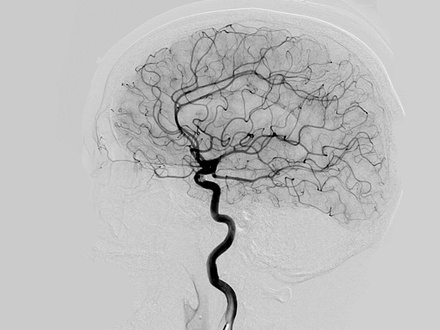

O Que é Arteriografia Cerebral?

Como é feito Arteriografia Cerebral?

Quais as indicações Arteriografia Cerebral?